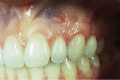

Gingival recession is an oral health problem that affects a large part of the population. Several treatments are suggested in the current literature; among them is the use of buccal fat pad grafting. The objective of this case report is to describe the treatment of a Miller Class I gingival recession using a nonpedicled buccal fat pad graft immediately after performing the surgery for buccal fat pad removal (bichectomy technique). First, bilateral surgical removal of the buccal fat pad was performed with the main objective of eliminating oral mucosa biting. The recipient site was prepared to receive a portion of the fat pad that was cut and macerated in a size that was sufficient to cover the recession. The patient was followed up at 15, 30, 60, and 365 days postsurgery, and the results showed an elimination of the oral mucosa biting and complete coverage of the gingival recession. It was concluded that the nonpedicled buccal fat pad graft is another option for the treatment of Miller Class I recessions.